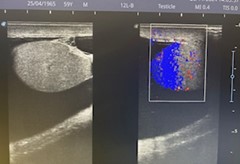

Estudio ecográfico testicular muy accesible sin preparación:

Caso 2: En escroto izquierdo imagen anecoica correspondiente a hidrocele a tensión, con coexistencia de trabeculaciones y loculaciones en el interior de hidrocele.